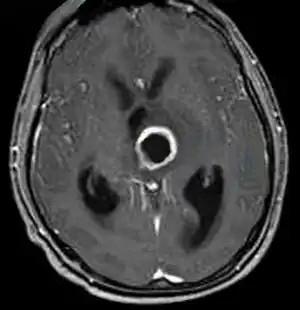

Thalamic abscess caused by streptococcus constellatus-image with contrast showing a thalamic ring-enhancing lesion in the left side of the brain

Clinically it is associated with abscess formation in the upper body and respiratory tract. It has also been found to be involved with pulmonary exacerbations in cystic fibrosis patients and can lead to toxic shock and limb amputation.[7]